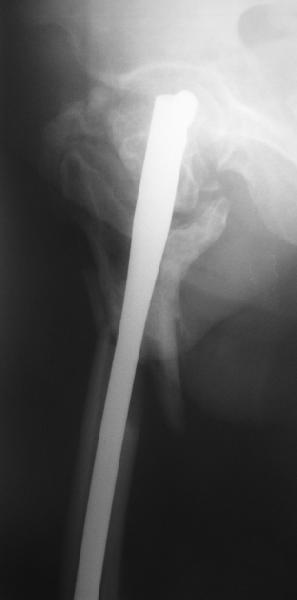

На прошлой неделе оперировали похожего пациента. 2 года после неудачного остеосинтеза PFN в другом регионе. После удаления остатков железа выявилось несращение вертельной области.

В такой ситуации важно устранить варусную деформацию. При использовании гвоздя это непросто. Поэтому в число рассматриваемых

Поскольку в нашем случае выявилась подвижность, мы наложили дистрактор таз-бедро на 3 дня, и сделали остеосинтез гаммой без остеотомии. То, что произошла "корригирующая остеоклазия" в подвертельной области, выявили после введения гвоздя. Пациент уже уехал домой, будем наблюдать.